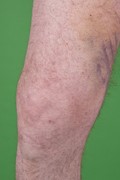

Modern scurvy

Rian A.A. Wijkmans and Koen Talsma

Journal of Surgical Case Reports, Volume 2016, Issue 1, January 2016, rjv168, https://doi.org/10.1093/jscr/rjv168